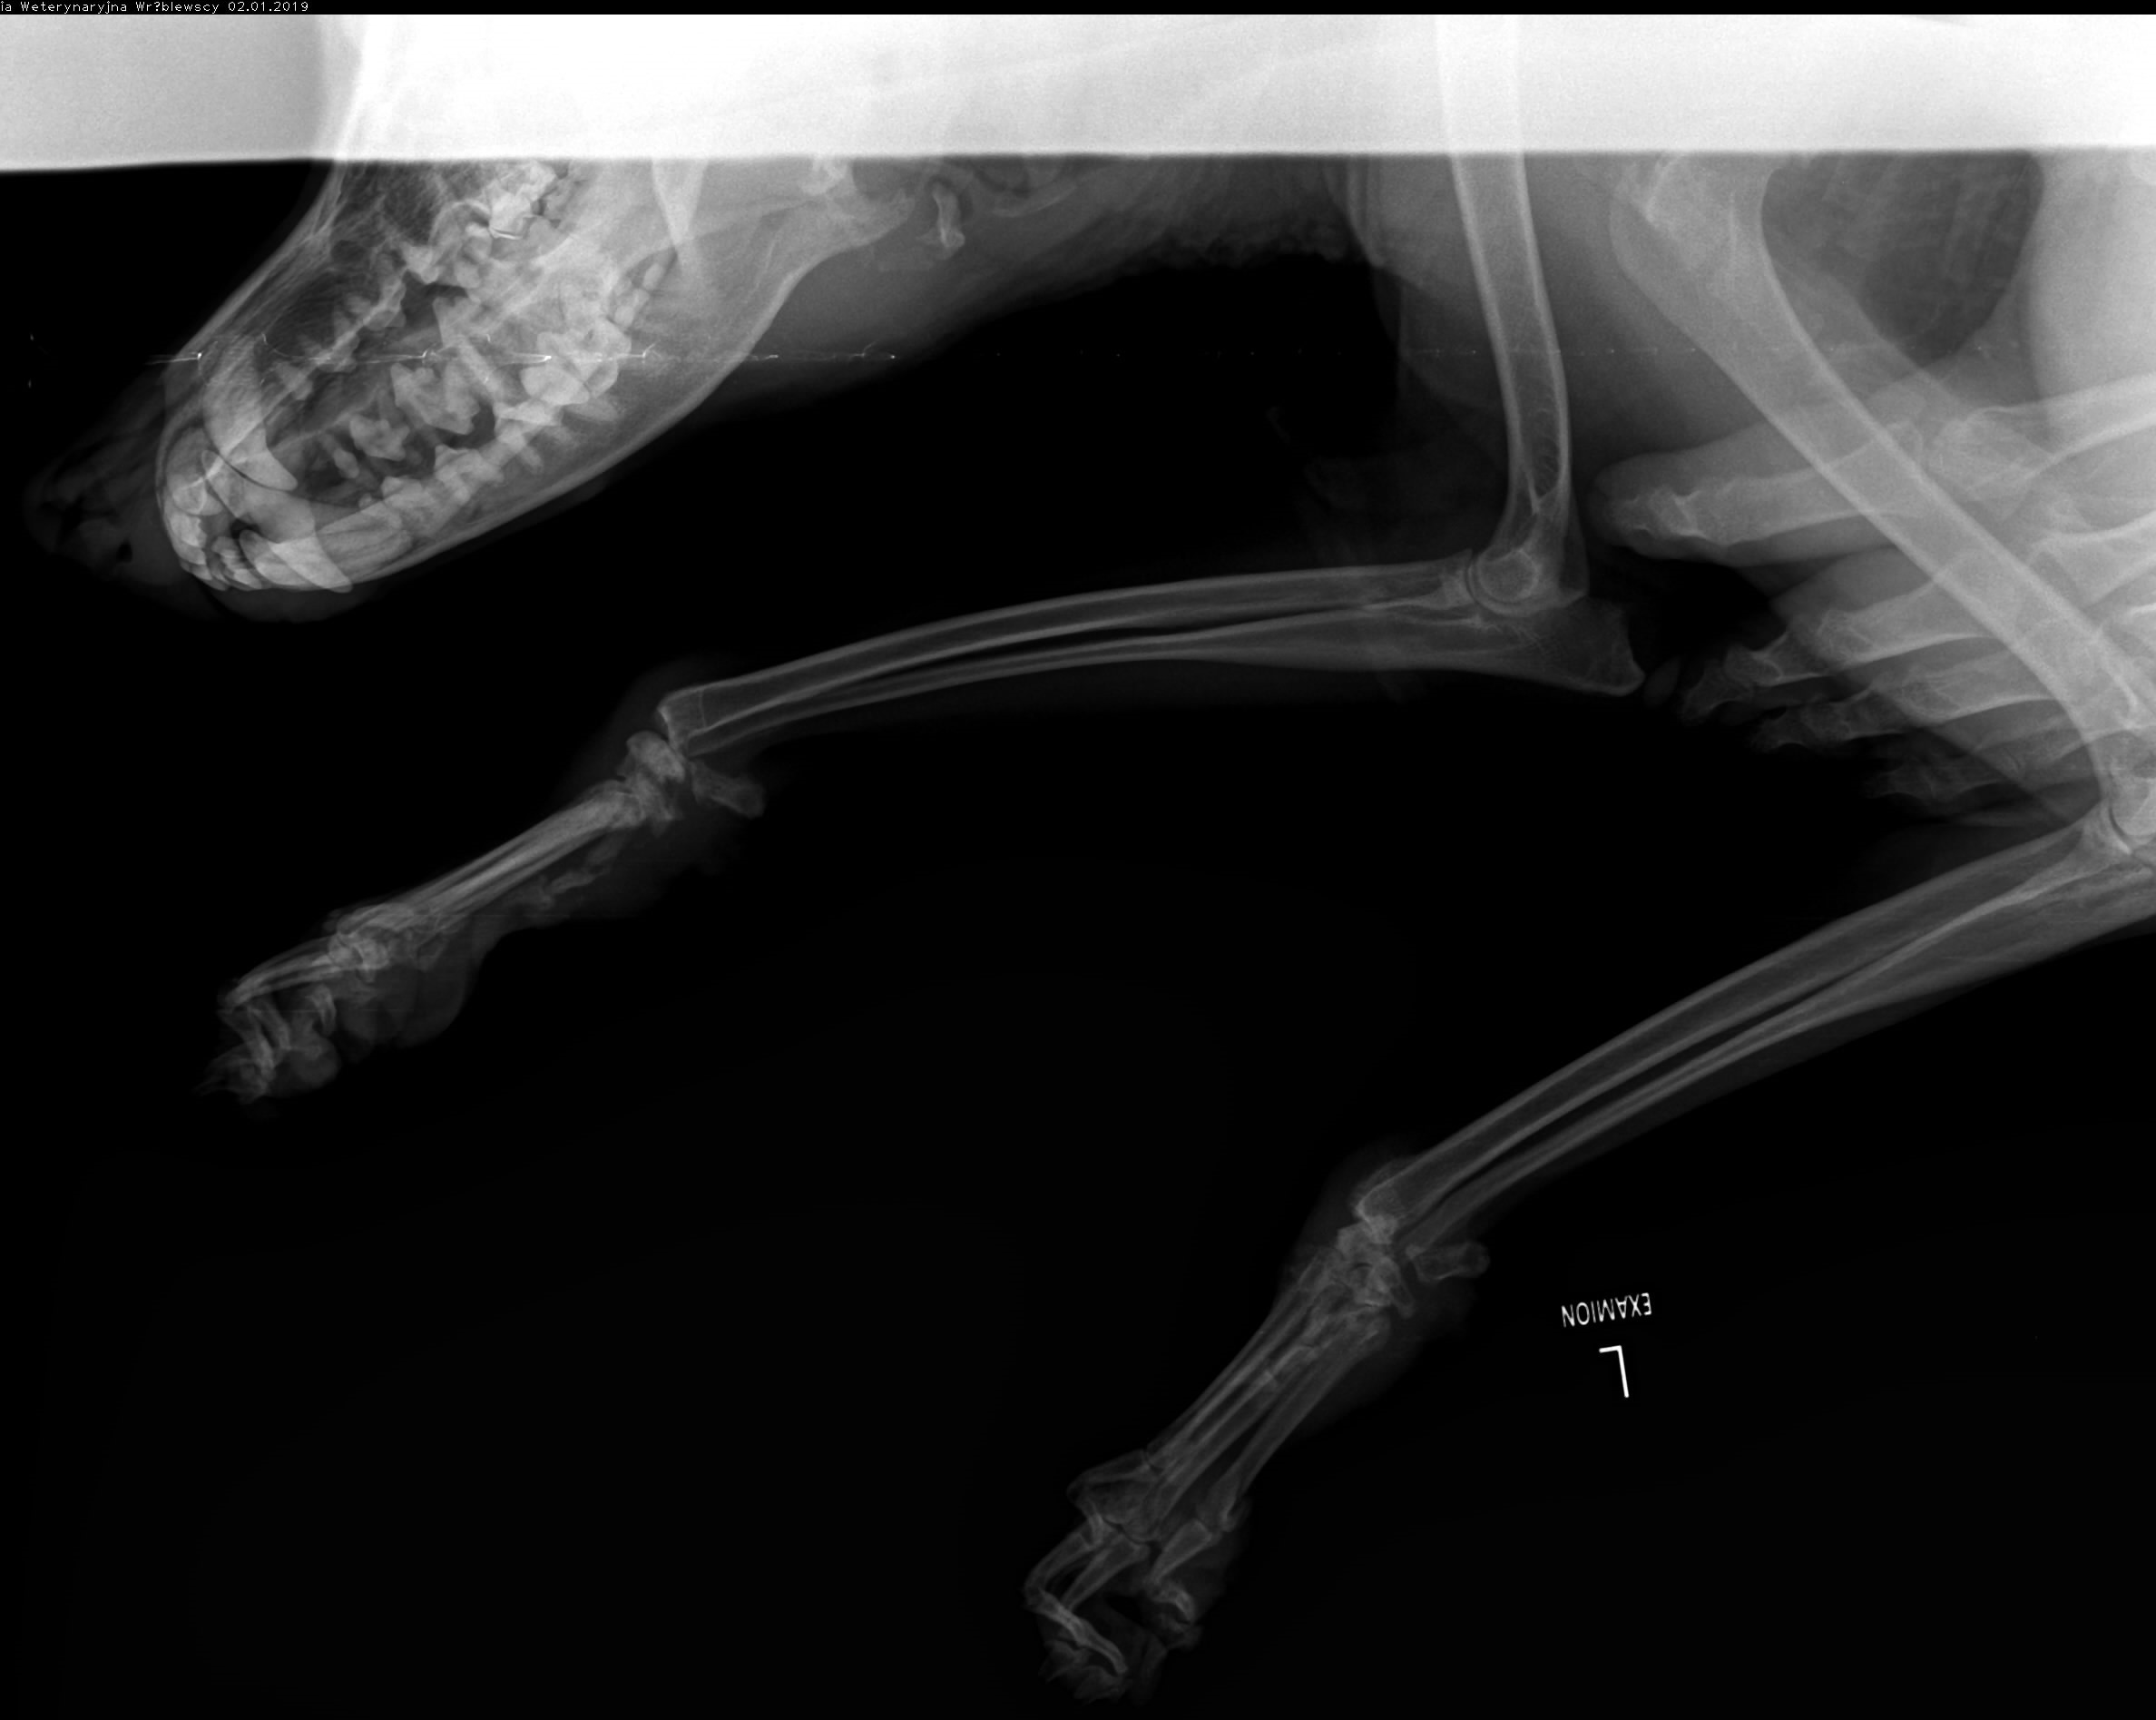

Leoś przebywał długie lata w schronisku w Raciborzu. Nikt Leosia nie chciał adoptować , taki był wycofany , bał się ludzi a w szczególności mężczyzn , co sami na sobie odczuliśmy jeżdżąc na wizyty zapoznawcze do hotelu w Gliwicach gdzie został przetransportowany. Leoś skradł nasze serca. Pomimo nie małych wątpliwości podjęliśmy decyzję o adopcji Leona i to była najlepsza decyzja. Leoś to piesek o wspaniałym charakterze , zrobił bardzo duże postępy , bez nas nigdzie się nie ruszy. Jesteśmy zmuszeni prosi o pomoc. Niestety okazało się , że nasz pupil zaczął mieć problemy z chodzeniem. Diagnoza lekarska była jednoznaczna, bez operacji Leoś przestanie chodzić. A opis lekarza ortopedy brzmiał tak : CAŁKOWITE ZWICHNIĘCIE STAWÓW NADGARSTKOWYCH , CAŁKOWITE ZERWANIE WIĄZADEŁ , DAWNE ZŁAMANIE KOŚCI PISZCZELOWEJ Z NIEPRAWIDŁOWYM ZROSTEM. LICZNE ZWYRODNIENIA STAWÓW, Załączam zdjęcia RTG .

Obecnie Leoś jest po operacji łapy przedniej lewej co ilustrują zdjęcia.